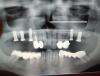

Два дня назад установили c права 2 – Implantatа…… 4 ка задета имплантатом!

При увеличении на снимке видно, срезало кончик зуба.

Зуб беспокоит? Сделайте компьютерную томограмму. ОПГ не всегда достоверно отображает соотношение зуб- зуб, зуб-имплантат и т.д.. Поставлено и правда по отношению к зубу не очень соосно, но и не факт что зуб задет.